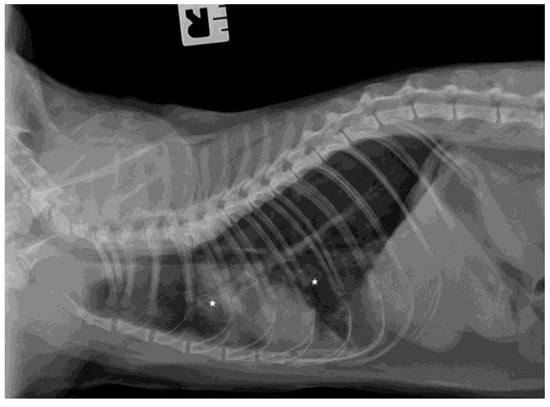

3.3. Ultrasound Examination and X-ray